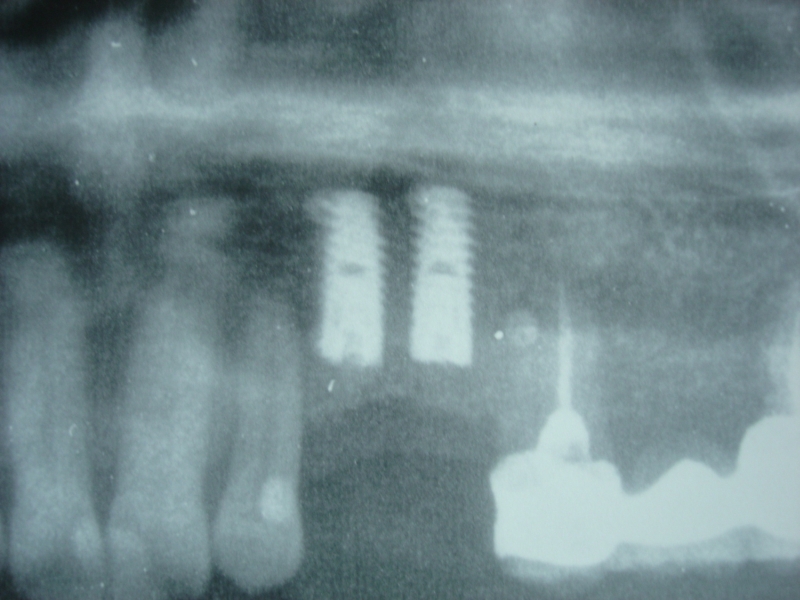

Initial x-ray showing bone loss around implants placed 5 years ago in another dental clinic